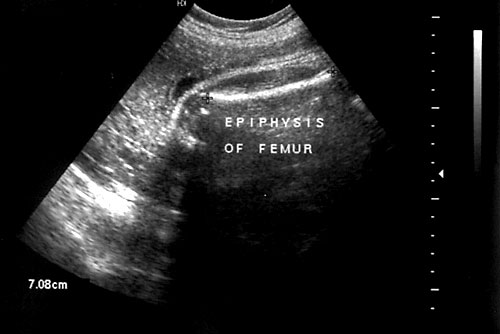

Proper measurement of femur. - Distal epiphysis not included in measurement. (Mahony BS, Filly RA. High-resolution sonographic assessment of the fetal extremities. J Ultrasound Med 1984;3(11):489-98. & Abrams SL, Filly RA. Curvature of the fetal femur: A normal sonographic finding. Radiology 1985;156(2):490.)

Femur at 36 weeks with epiphysis seen to left of photo at arrow.